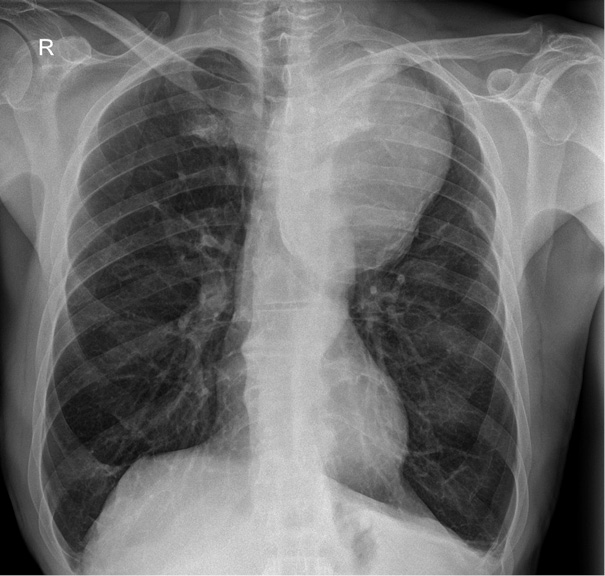

Physical examination findings were unremarkable, with no audible bruits, masses, or neurological deficits. Vital signs on admission were as follows: blood pressure 150/90 mmHg, heart rate 60 bpm, respiratory rate 18/min, oxygen saturation 96% on room air.

The detection of a mediastinal mass prompted differential diagnostic considerations, primarily focusing on two major possibilities: (1) mediastinal tumor formation associated with lymphocytic infiltration due to leukemia or other oncological masses, and (2) a giant vascular aneurysm. To delineate the etiology, a two-dimensional CT scan of the thoracic aorta was performed, as shown in Figure 2, revealing a large aneurysm in the distal post-arch segment of the descending aorta. The observed mass corresponds to a giant aneurysmal dilation.

The aneurysm measured 14.08 × 10.04 cm in its maximum transverse diameters. No chronic thrombus was identified within the tunica media, nor was there any evidence of dissection. The proximal ascending aorta measured 38 mm in diameter. Figure 3, which depicts a three-dimensional CT reconstruction, delineates the anatomical relationship of the aneurysm with the aortic arch, the left subclavian artery, and the descending thoracic aorta. The aneurysm was localized, with no involvement of the proximal left subclavian artery or its orifice. The distal portion of the aneurysm did not extend to spinal or intercostal branches. The remainder of the aorta, including the abdominal segment, appeared normal. The primary clinical impact of the aneurysm was attributed to a significant mass effect, leading to compression of the trachea and bronchi as well as potential irritation of the left phrenic nerve secondary to mediastinal compression.

GDTAA often presents with non-specific symptoms that are primarily due to mass effect rather than rupture [19]. Common clinical manifestations include dyspnoea, cough, chest pain and dysphagia due to compression of adjacent structures such as the trachea, bronchi and oesophagus [9]. In the case presented, the patient had recurrent syncope, persistent cough and fatigue, which correlated with significant deviation of the trachea and compression of the airway structures on imaging [20].

CT angiography remains the gold standard for the diagnosis and assessment of the extent of GDTAA [21]. It allows high-resolution visualisation of the size and morphology of the aneurysm as well as the anatomical relationships with the adjacent structures [21]. In this case, CT imaging confirmed a massive aneurysm with significant displacement of the trachea and compression of the bronchi, thereby emphasising the crucial role of modern imaging in surgical planning [21].